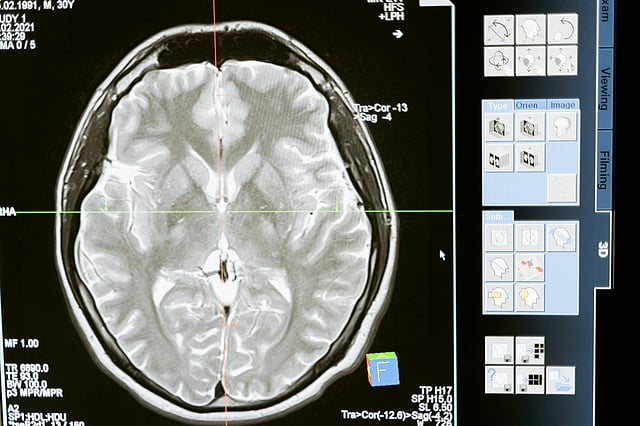

In the last few months, there has been an alarming increase in stroke cases in Telangana. What makes this a bigger cause for concern is that youngsters are suffering strokes. In light of World Stroke Day on October 29, Dr Gaurav Thukal, co-founder and COO of HCAH - Healthcare at Home, a medical rehabilitation centre in the city, talks about precautions, the importance of rehabilitation and recovery centres for stroke patients.

Dr Gaurav underscores that hypertension is bad news because high BP can lead to bleeding of the brain and this in turn can cause a stroke. For youngsters, the two main causes of strokes are smoking and stress, says Dr Gaurav.

But the moment you start delaying it, the recovery stops after 180 days.” Elaborating on the importance of the brain, the doctor states that it is the only organ that dies if it doesn’t get blood. “The Day 7 to 21 window is a narrow window of neuroplasticity.